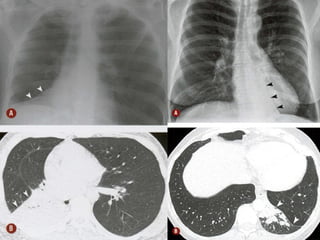

O documento discute vários conceitos radiológicos incluindo consolidação, atelectasia, nódulos, pseudocavidades e padrões intersticiais, fornecendo definições, sinais e diagnósticos diferenciais para cada tópico. Ele também discute a redução da atenuação pulmonar e fornece um link para mais informações.